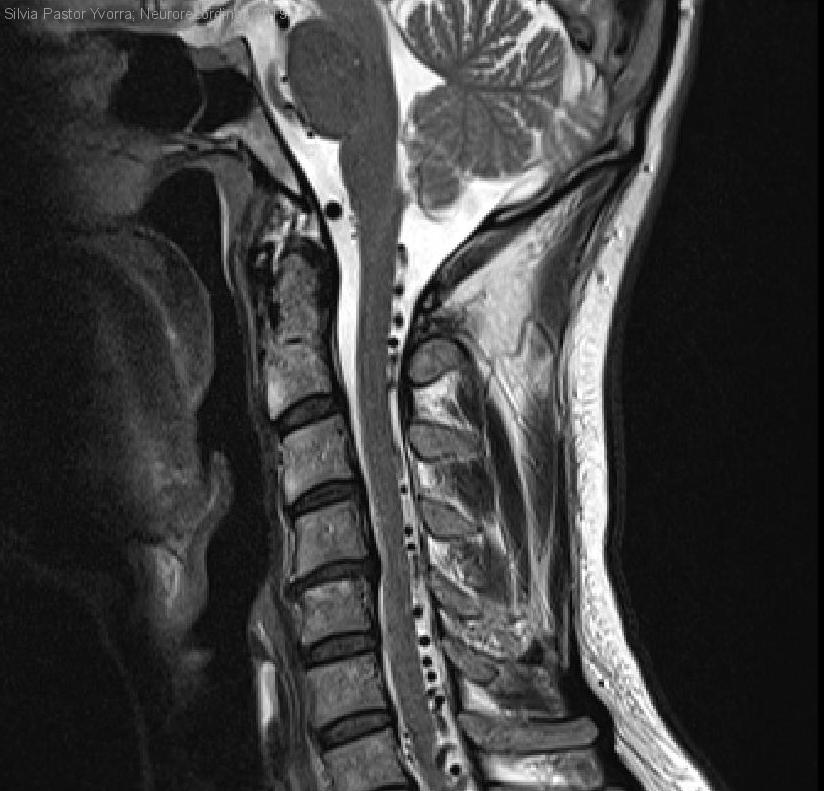

Hombre | 42 años

Diagnóstico final: Malformación arteriovenosa intramedular nivel T5-T8

Paciente con antecedentes de episodio de afasia autolimitado, fumador de tabaco y consumo de alcohol ocasional, que presenta debilidad en extremidad inferior derecha y rigidez de un año y medio de evolución. Posteriormente refiere urgencia...